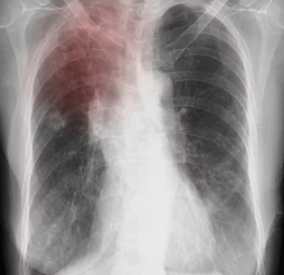

| 흉부 X-ray | 폐 병변, 섬유화, 공동 등 확인 |